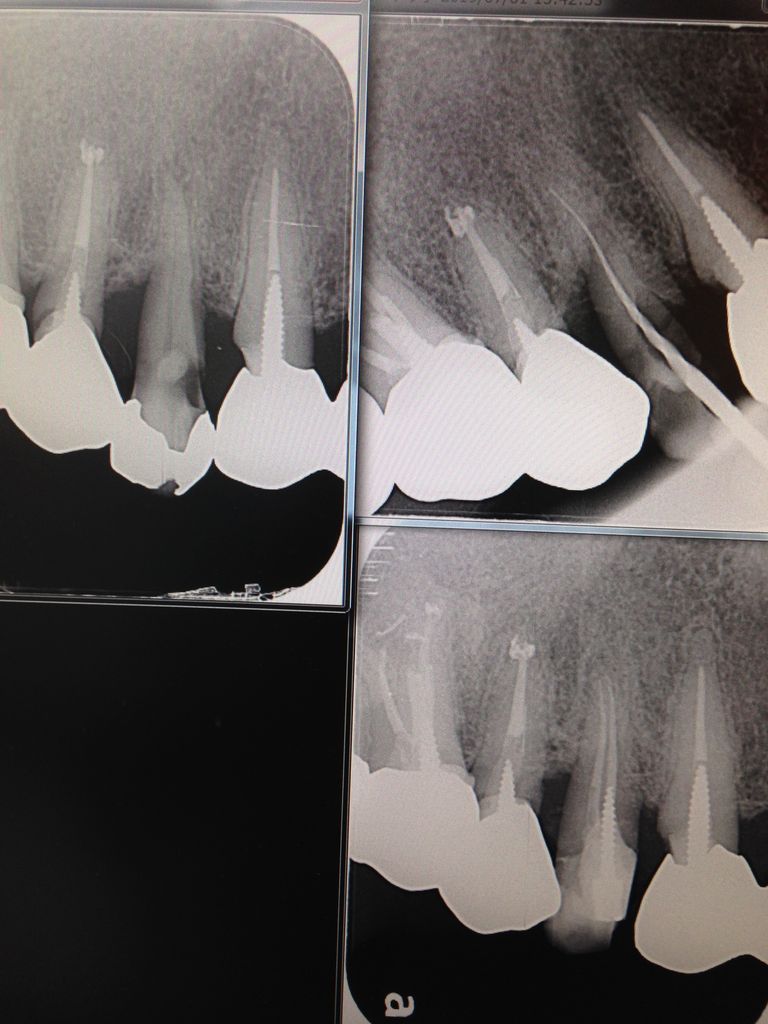

下が根の先で、真ん中にある青く見えるのが神経。

右下の赤いのは骨。

歯の根の先には、歯根膜という薄い靱帯 と骨があります。

左下は骨でなくて、青く見える炎症性の細胞が沢山集まっています。

青い点々です。

骨でなくて、柔らかなお肉なので

レントゲンで黒く見えます。

ここが根の病気の場所。

骨🦴は細菌とは戦えないので、炎症性の細胞が代わって戦っているんです。

でも神経の中にも青く見える細胞が集まっていますよね?

て、ことは生きてます。

根の先に病気があるけど、神経はまだ生きてます。

健康ではないけど。

だから、麻酔をしないと痛いんです。